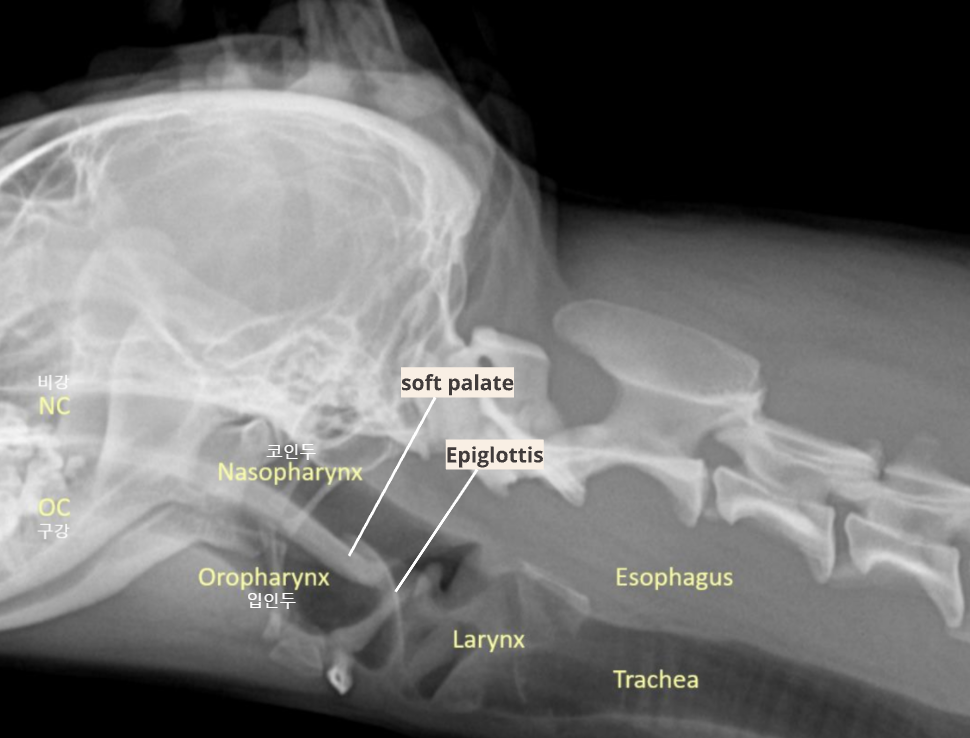

| Upper respiratory system |

![]() |